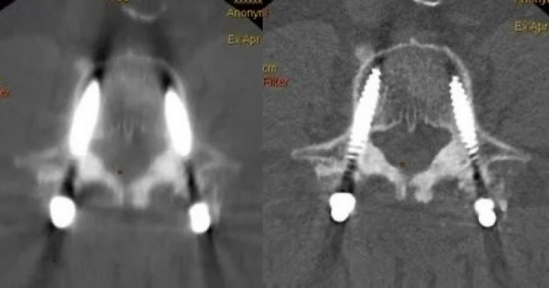

該設(shè)備還能利用能譜掃描更好地去顯示組織結(jié)構(gòu),提高小病灶的檢出率,提高靜脈成像質(zhì)量,消除金屬偽影,反映組織器官病變的特點和規(guī)律等。